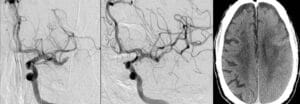

Topic: Cerebral Hyperperfusion Syndrome Author: Ayah Bozeyeh Editor: Ihda Bani Khalaf Reviewer: Ethar Hazaimeh Keywords: Blood flow, Stroke, Pressure, Circulation, Autoregulation, Cerebrovascular disease Overview Cerebral Hyperperfusion Syndrome (CHS) is a rare but potentially devastating complication characterized by an abnormal and excessive increase in cerebral blood flow, which can lead to neurological deterioration, brain injury, and even death. It often occurs following revascularization procedures that aim to improve cerebral circulation, such as intracranial angioplasty, stenting, carotid endarterectomy, and carotid artery stenting. [1] As the utilization of these procedures increases, particularly for patients at high risk for ischemic stroke, there is a […]